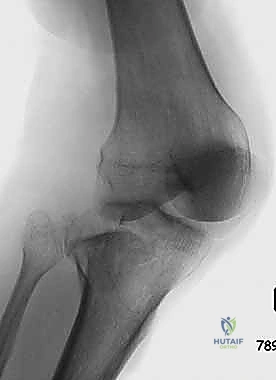

2. التصوير الإشعاعي (X-rays)

الخطوة الأولى هي التقاط صور أشعة سينية من عدة زوايا (أمامية خلفية، وجانبية). تعطي الأشعة السينية فكرة عامة عن وجود الكسر وموقعه، لكنها غير كافية لتقييم الكسور ثنائية اللقمة المعقدة.